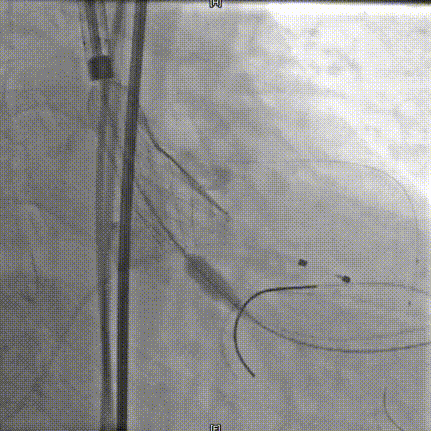

20mm球囊预扩

瓣膜定位

AV26瓣膜释放到工作位

术中20mm球囊预扩可见轻微腰征,轻微瓣周漏,左冠充盈速度减慢,为保证患者安全,决定行冠脉保护,预防冠脉阻挡风险。选择AV26瓣膜,TaurusElite AV26瓣膜送至主动脉弓,输送系统轻松过弓及跨瓣,精准定位无冠窦最低点。